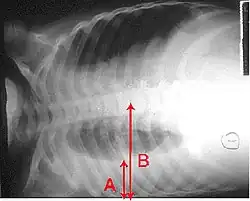

A: Flüssigkeitsspiegel

B: Grenze der rechten Lunge und der Pleurahöhle

Auf der beim Verdacht auf das Vorliegen eines Pleuraergusses empfohlenen Röntgenaufnahme des Brustkorbs sind Pleuraergüsse in der p.-a.-Thoraxaufnahme meist ab einem Volumen von 200–300 ml, bei der seitlichen Aufnahme ab 50 ml erkennbar.[2]:S. 380 Typisch ist bei einer im Stehen angefertigten Aufnahme eine nach lateral (außen) ansteigende Verschattung (dargestellt durch die den Erguss begrenzende Damoiseau-Ellis-Linie, auch Ellis-Damoiseausche Linie[5] genannt[6]).